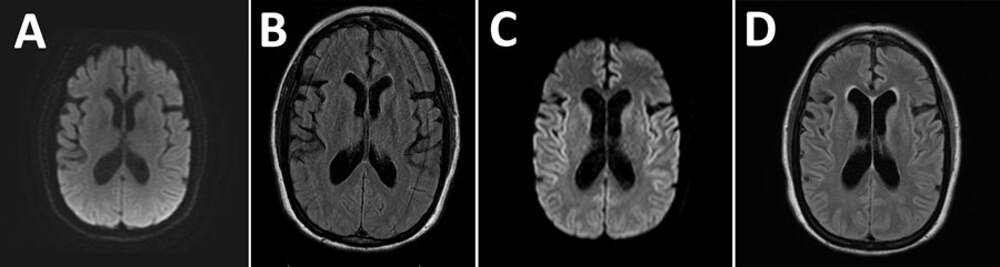

Недавно в журнале BMC Psychiatry описали случай 42-летней женщины, у которой после относительно легко перенесенного ОРВИ развился синдром Капгра, при котором пациент считает, что близких людей заменили самозванцы-двойники. В описываемом случае «самозванцем» стал муж пациентки. Лечение